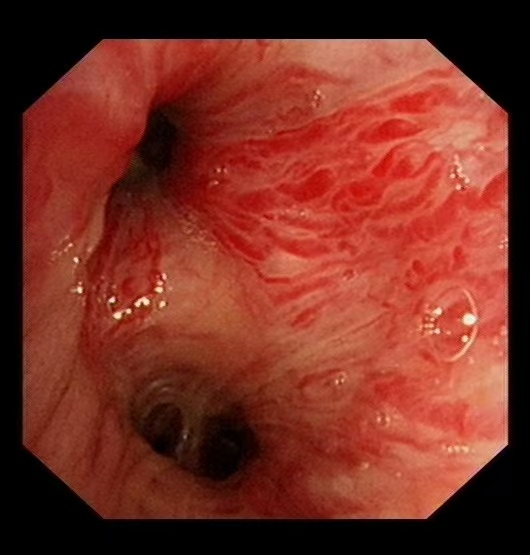

58歲的汪先生(化名)因大咯血入院,雖生命體征平穩(wěn),但出血癥狀持續(xù)未緩解。經(jīng)支氣管鏡檢查發(fā)現(xiàn),其左側(cè)支氣管內(nèi)存在浸潤性新生物,表面血管扭曲、血供豐富,隨時(shí)可能再次出現(xiàn)大咯血,病情十分兇險(xiǎn)。